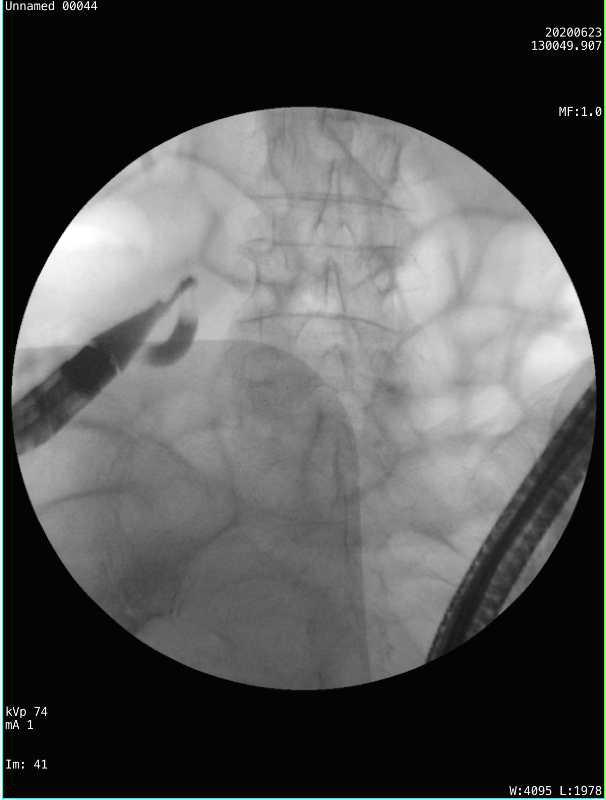

2、内镜逆行性阑尾造影术

X线下,在阑尾腔内注入造影剂显示阑尾腔的形态,并确认有无阑尾穿孔。